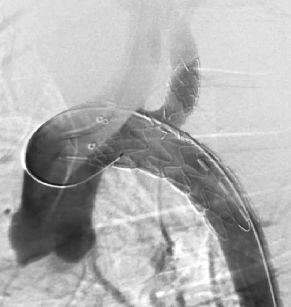

case 2

患者男性,78岁,胸主动脉瘤,采用双开窗技术(LSA+LCCA)重建分支。Futhrough系统在直径较小的血管中(成角小、行程长)实现精准穿刺,术后12个月随访显示支架通畅,无内漏或移位。